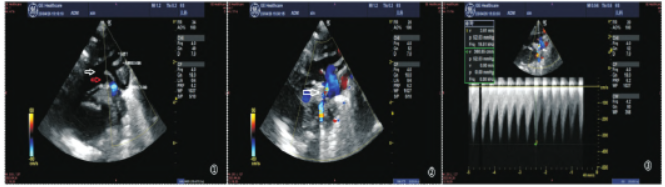

升主动脉向上形成两个左位主动脉弓,上方为第四弓,下方为第五弓,第四弓发出三大分支,位置正常,远端为一盲端,与降主动脉无连接(图①)。第五弓远端与降主动脉连接处狭窄,宽约1.5mm(图②),峰值速度360cm/s,峰值压差52mmHg(图③),该处周围可见多支侧枝血管,降主动脉内径正常,宽约6.0mm,血流频谱显示呈小慢波。

全心内径增大,各心脏瓣膜形态、回声、活动均未见异常。房间隔卵圆孔回声分离约1.8mm,另于房间隔可见2束约1mm 的连续性中断。室间隔回声连续。左室壁搏动弥漫性减弱,左室收缩功能:EF35%。超声印象诊断:主动脉弓发育异常,永存第五主动脉弓并第四弓离断,降主动脉缩窄,房间隔缺损(继发孔型两处),卵圆孔未闭,心功能下降。

图1-3 超声胸骨上主动脉弓长轴切面检查:图①可见第四主动脉弓(白色箭头所示),及其所发出的头臂干、左侧颈总动脉、左侧锁骨下动脉,三条头臂动脉远端无延续。第五主动脉弓(红色箭头所示);图②箭头所示为第五弓远端与降主动脉连接处狭窄;图③示第五弓与降主动脉连接处狭窄血流频谱。